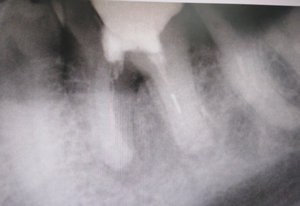

Был нарощен, на штифте, передний нижний зуб. Он выпал вместе со штифтом. В клинике сказали, что можно поставить только металло-керамическую коронку, на культевую вкладку. Сделали снимок, выяснилось, что у меня киста на корне зуба - семь миллиметров.

Можно ли ставить коронку на зуб с кистой? Какие ещё есть варианты?

Этот зуб необходимо удалить. Такая большая киста не лечится. Резекция верхушки также не поможет.